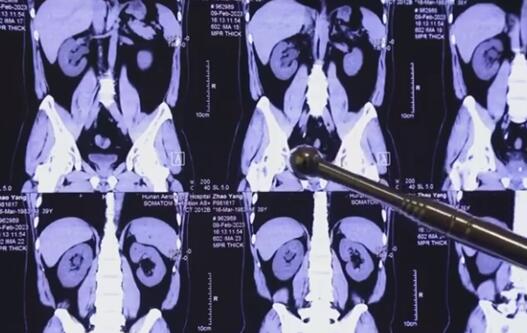

據(jù)了解,趙先生患結(jié)石已經(jīng)多年,之前一直沒當(dāng)回事,今年復(fù)發(fā)檢查后發(fā)現(xiàn)腎臟、輸尿管內(nèi)都有結(jié)石。